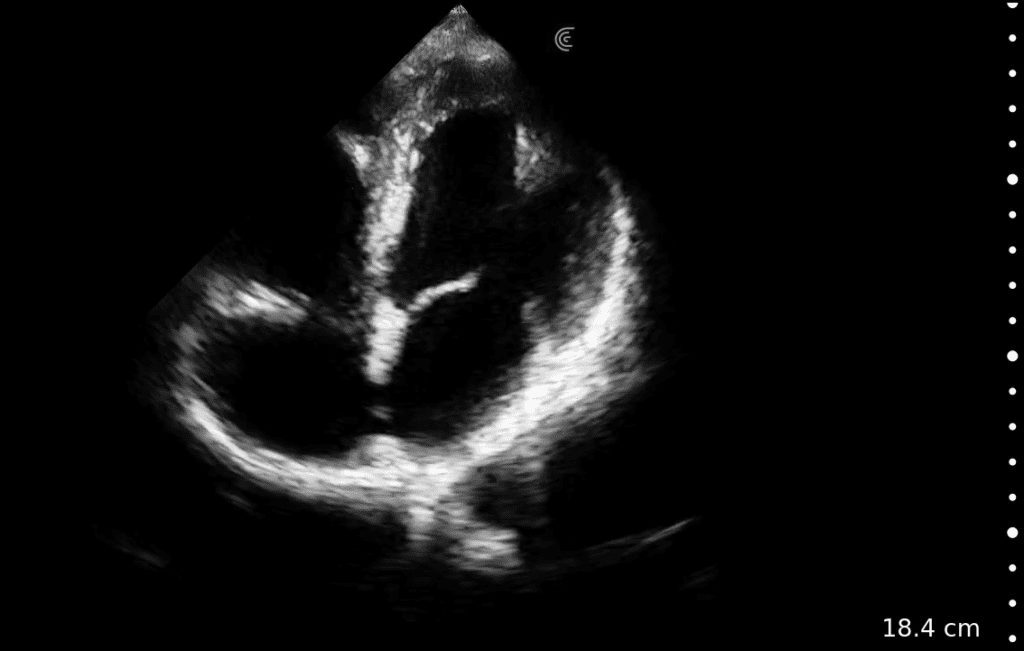

• Perform goal-directed echocardiography at the bedside

Cardiac

Quick Cardiac

Comprehensive package for precise cardiac function assessment.